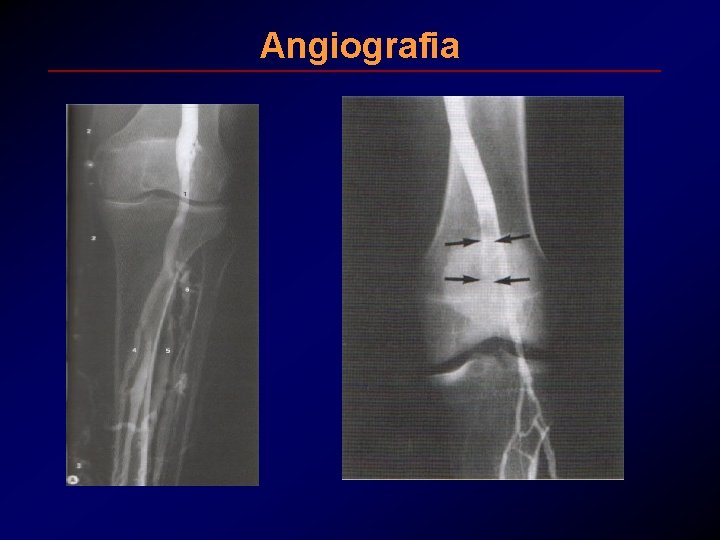

Angiografia

Angiografia • L’angiografia polmonare è una flebografia ascendente con mezzo di contrasto per lo studio della cava inferiore e della vascolarizzazione polmonare. E' il gold standard per la diagnosi di embolia polmonare. Le indicazioni riguardano: 1) pazienti con scintigrafia polmonare scarsamente diagnostica ma con quadro clinico altamente sospetto, 2) pazienti in cui sia indicato il trattamento trombolitico o l'embolectomia, 3) pazienti in cui sia necessario confermare la diagnosi per un notevole rischio emorragico legato all'impiego del trattamento anticoagulante per via sistemica.